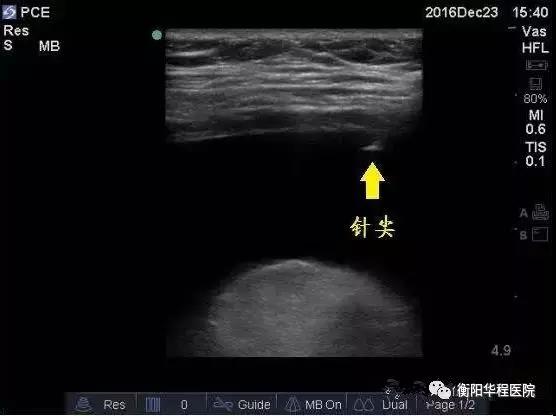

圖3  采用平面內(nèi)超聲引導(dǎo)技術(shù)可實時觀察到針尖位置